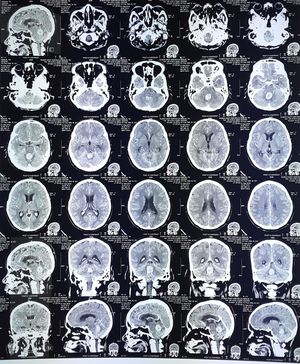

Ct scan with contrast

Male 52 yo had dizzines,headache,nausea vomitus 1 month also have a fever

Tumor between the midbrain and cerebellum?

something's occupy forth ventricle between pond and cerbellum

Blood in ventricle

ventricle dilated

There is a cerebellar tumor

?Meningioma

Subdural hemorrhage